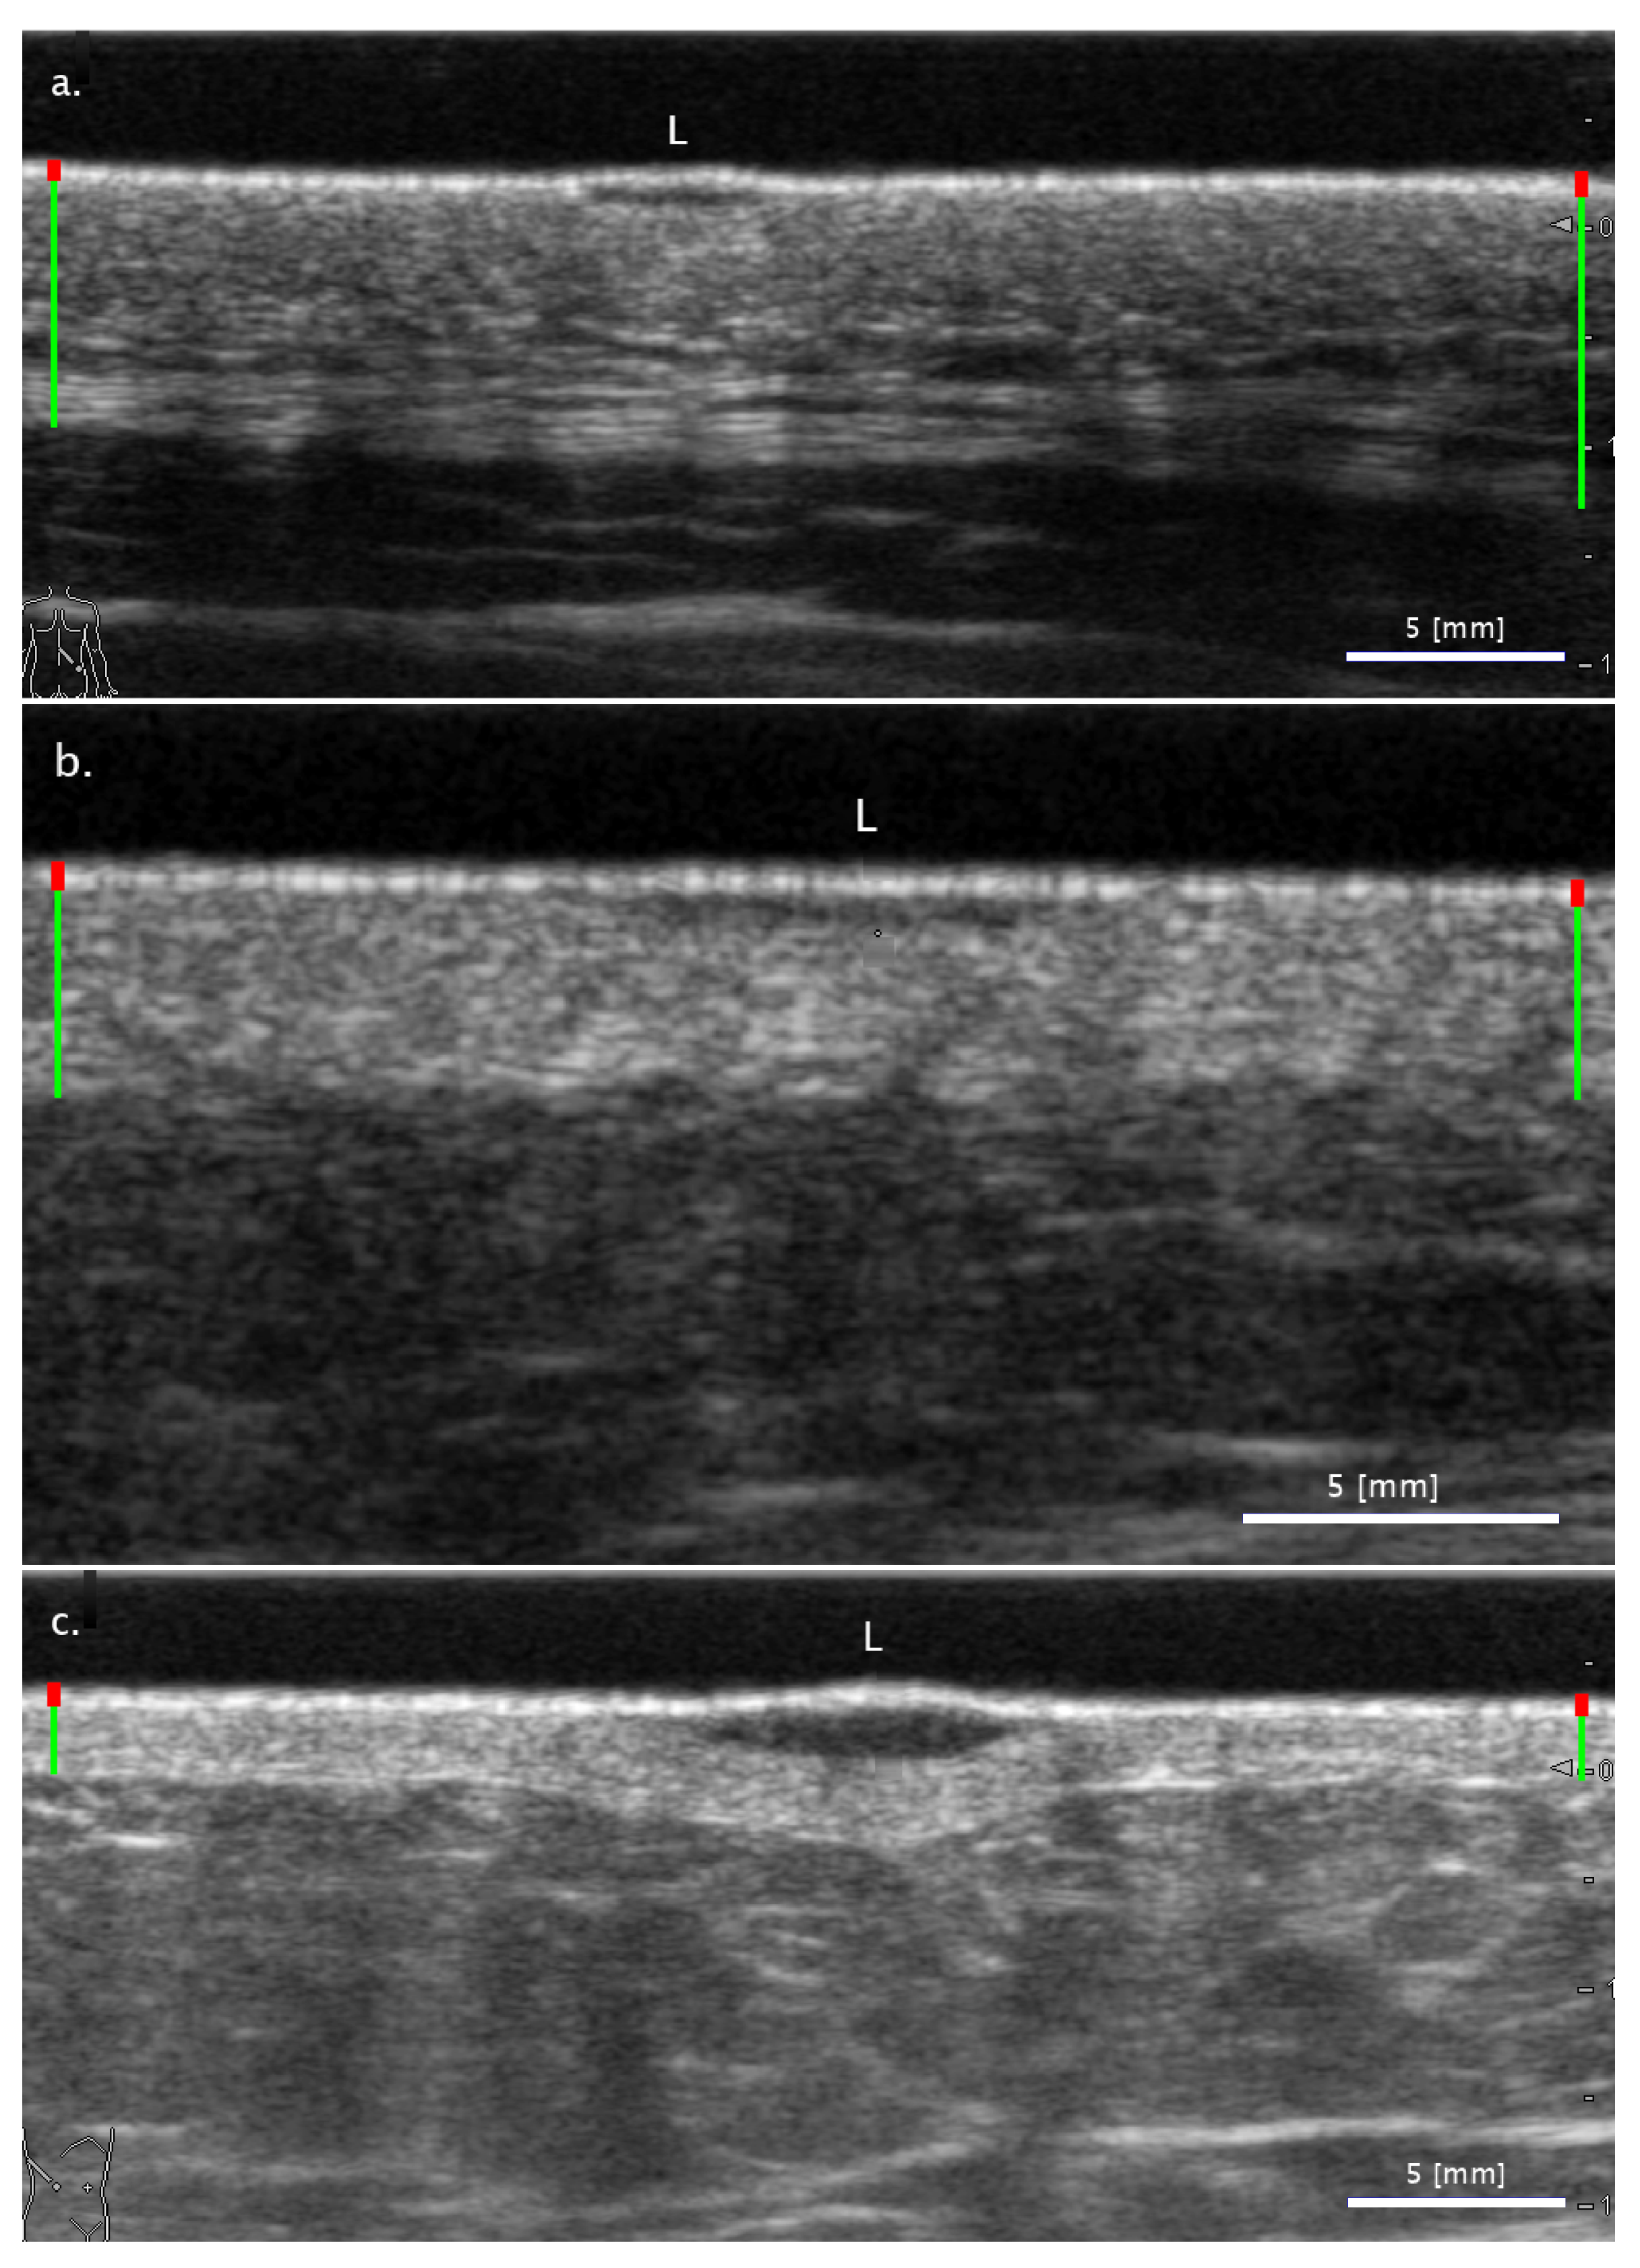

3.2. Comparison of FA and SA Classification Performance with Representative Images

3.2.1. Cases When FA Fails While SA Methods Perform Correctly

3.2.2. Cases When the Two SA Methods Return Different Classifications

3.2.3. Cases When the SA Methods Both Fail While the FA Method Performs Correctly

3.3. Sensitivity of Classification to Changes in Lesion Segmentation